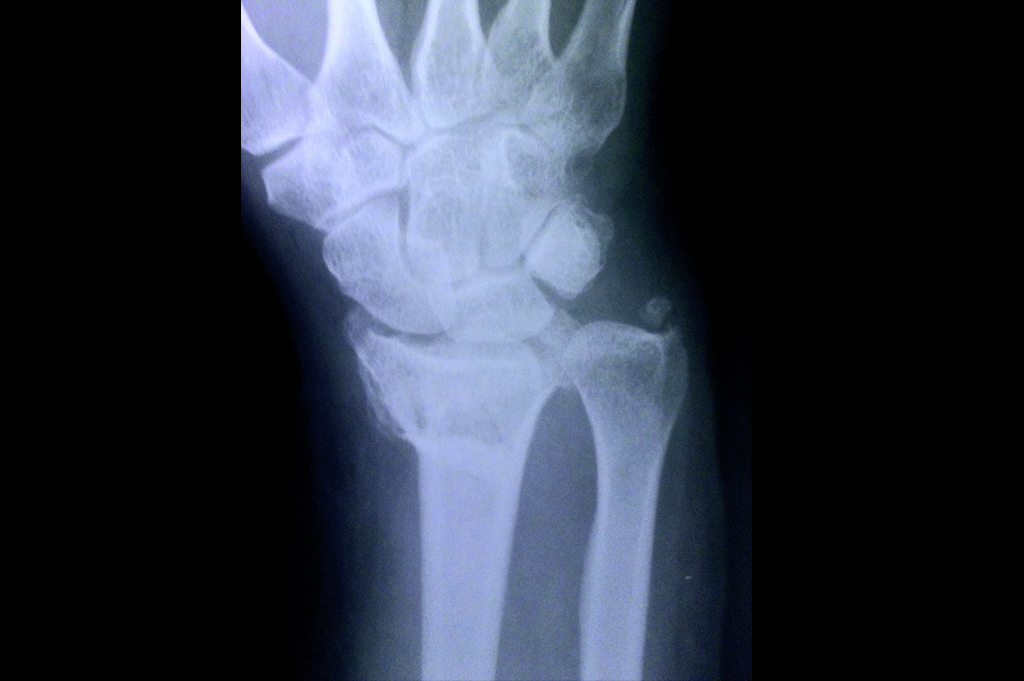

Scaphoid

Lower Radius